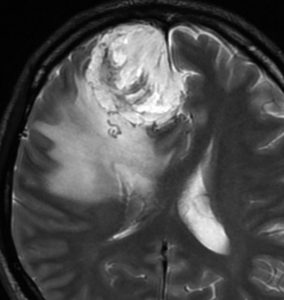

angiomatous meningioma WHO grade 1 血管腫様髄膜腫

術前検査ではまるで膠芽腫のような画像です。でも,開けてみれば髄膜腫ということはすぐにわかる肉眼所見です。硬膜の至る所から腫瘍血管が流入して出血性腫瘍です。